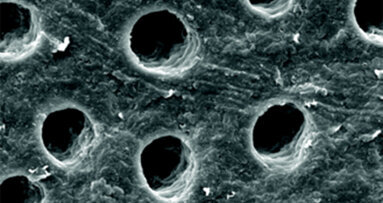

Piezochirurgie představuje v kostní chirurgii k měkkým tkáním dostatečně šetrnou techniku založenou na ultrazvukových mikrovibracích. Vyvinuta byla na základě myšlenky italského parodontologa, dentoalveolárního chirurga a implantologa Tomaso Vercellotti v roce 1998 a klinické zkoušky na území České republiky byly zahájeny v roce 2002. Po celou dobu existence této technologie docházelo k jejímu vývoji, takže v současné době je velmi efektivní a v mnoha směrech překonává hranice tradičních chirurgických technik. Četné histologické práce o hojení kostních ran a utváření kostí na pokusných zvířatech ukázaly, že odpověď tkání je v případě použití piezochirurgie příznivější ve srovnání s tradičními technikami řezání kostí za použití rotačních tvrdokovových nebo diamantových nástrojů32. Dokazuje to i závěr našeho experimentu provedeného v roce 2010, kdy jsme vyšetřovali histologicky odpověď naléhající mozkové tkáně pokusných zvířat, u nichž jsme preparovali kalvu v blízkosti jedné z hemisfér rotačním nástrojem a na straně druhé pomocí piezochirurgie17. Porovnáváme-li histologicky kostní okraje fragmentů získaných během operace provedené ultrazvukovým přístrojem a klasickou pilkou, nevykazuje mikroskopické vyšetření tkáně preparované pomocí piezochirurgie znaky nekrózy; na kostním povrchu jsou zachovány osteocyty s vitálními jádry. Tím je chráněna i vitalita zubu v blízkosti preparace19.